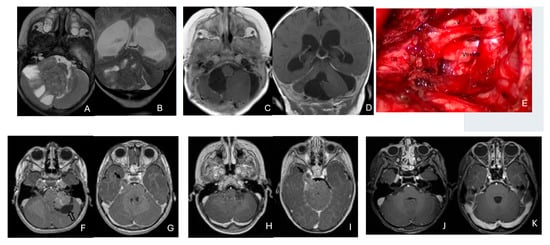

Objectives: Atypical teratoid/rhabdoid tumors (ATRTs) are rare, malignant central nervous system (CNS) neoplasms that predominantly affect infants and young children. While ATRT arises throughout the CNS, its extracranial counterpart, malignant rhabdoid tumor, occurs in other organs. A single-institutional cohort is reviewed to map anatomic distribution of pediatric ATRTs and to integrate a literature review to contextualize ATRT histogenesis from anatomical and embryological perspectives. Methods: A retrospective review was conducted on a cohort of 50 pediatric patients with ATRT treated over 20 years. Demographic, surgical, and neuroimaging data were correlated to define tumor location, extent, and compartmental involvement. A focused literature review synthesized molecular subclassifications and proposed cells of origin/cytogenesis. Results: Of the 50 ATRTs, 18 (36%) were infratentorial, 15 (30%) supratentorial, 11 (22%) in the pineal region, and 6 (12%) in the spinal compartment. Among infratentorial tumors, 10 were centered in the fourth ventricle, with or without extension into the cerebellopontine angle (CPA) cistern; the remainder arose in the CPA. Among ATRTs of the cerebral hemispheres, 3 showed bi-hemispheric involvement crossing the falx cerebri. ATRTs of the pineal region predominantly originated from the superior medullary velum. These topographic data were corelated with embryological and molecular information available in the literature. Conclusions: ATRTs arise across diverse neuroanatomical compartments—including intraparenchymal, intraventricular, extra-axial, and extradural sites—underscoring biological heterogeneity. Inactivation of SMARCB1 is the defining molecular event and principal oncogenic driver, although the upstream mechanisms precipitating these alterations remain incompletely resolved. Molecular subgroups—ATRT-TYR, ATRT-SHH, and ATRT-MYC—display distinct age distributions and anatomic predilections, implicating developmental context in tumor initiation. The characteristic cellular admixture of rhabdoid cells with mesenchymal and/or epithelial differentiation, together with intra- and extra-axial and occasional extradural presentations, supports a model in which at least a subset of ATRTs may originate from neural crest-derived lineages, despite little or no neural crest contribution to brain parenchyma development. Neural plate border progenitors with bipotent features represent a plausible intraparenchymal cell of origin. Definitive resolution of these origins and the mechanisms of SMARCB1 disruption will require integrated approaches. Further investigations are warranted to clarify these mechanisms.